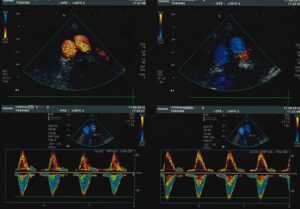

L’esame ecografico dell’aorta addominale ha principalmente lo scopo di identificare per tempo la dilatazione ( aneurisma ) di questa grossa arteria. L’esame consiste nell’appoggiare una sonda ecografica sull’addome, da sotto lo sterno fino all’ombelico, e nella registrazione delle immagini e dei grafici doppler.

L’esame semplice e privo di radiazioni serve pertanto ad individuare tale patologia, seguirla nel tempo e, quando necessario, porre l’indicazione ad un intervento chirurgico ( aneurismectomia ). Con la metodica in oggetto, in casi selezionati, si può anche verificare la possibilità di un’intervento mediante applicazione di endoprotesi.